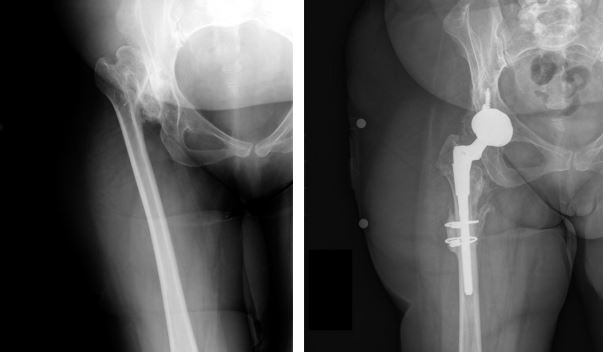

方法:在一项回顾性研究中,我们评估了24例非骨水泥全髋关节置换术的结果和并发症,共 24例(20例女性和4例男性)Crowe型IV型发育不良。采用非骨水泥全髋关节置换术结合转子下缩短截骨术,将髋臼假体放置在解剖学旋转中心的水平处。术后平均随访4.8年,对患者进行评估。

结果:平均的Harris髋关节评分从术前的 43 分提高到了最终随访时的 89 分(p <0.01)。 28 个髋中有12个(43%)发生了早期或晚期并发症或再次手术。28例转子下截骨术中有2例(7%)发生骨不连。有1例股骨柄松动,1个髋臼假体松动,1个髋臼内衬脱离。术后有4例髋关节脱位。在最后一次随访时,其余组件均固定良好。未发现坐骨神经损伤的病例。

结论:在髋关节发育不良继发高位髋关节脱位的患者中,非骨水泥全髋关节置换术结合股骨转子下缩短截骨术可以成功固定植入物和获得截骨部位愈合,平均术后Harris髋关节评分89分。 然而,这一类患者术后的并发症发生率显著高于骨关节炎的初次全髋关节置换术。